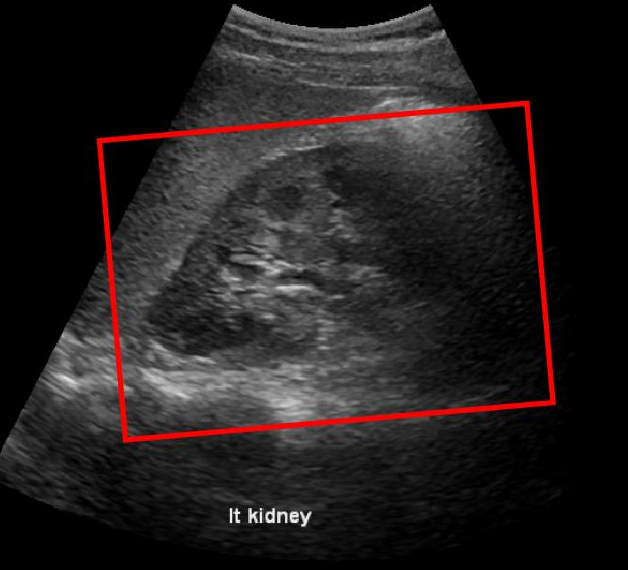

To build our binary classification models from training images, we swept the field of view (FOV) to generate many overlapping patches of varying sizes (see Fig. 1) that satisfied clinical guidelines on average adult kidney dimensions and aspect ratio [8]. We downsampled these ROIs to a common size and were further binned into two classes based on their overlap with ground truth annotations. We used Dice similarity coefficient (DSC) as the metric and a threshold of 0.8 (based on visual and clinical feedback) was used to generate positive and negative class samples. This was followed by feature extraction and model building.

Refer to caption

(a)

(b)

(c)

Figure 1: (a) Sample Generation (b) Positive patches (c) Negative patches